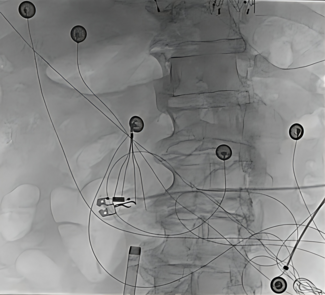

Brief Communication

Clinical Image